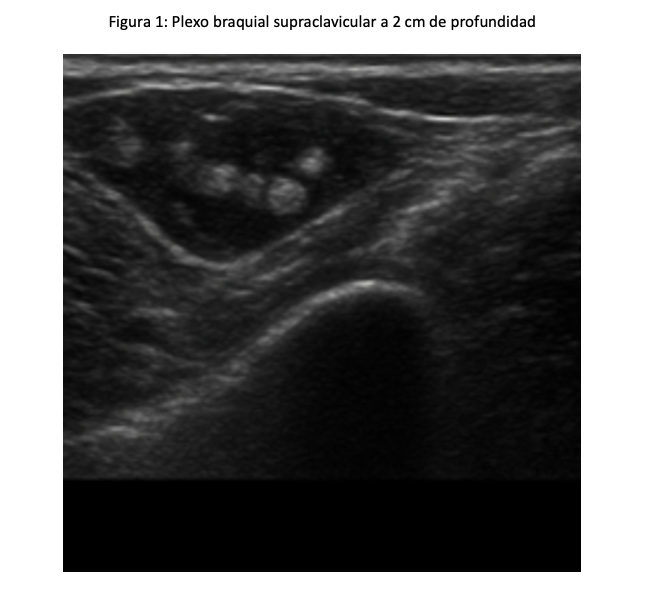

Se planificó un BPBS derecho ecoguiado con ultrasonido con transductor lineal 3.5 MHZ, con ganancias al 60 %; se realizó el cálculo de volumen de Ropivacaina a 0.2 mL por kilogramo de peso, el niño pesó 65 kg, así que se le administró 13 mL y fue a una concentración de 0.5 % con un total de 65 mg, se tomó 8.6 mL de Ropivacaina al 0.75 % y 4.4 mL de agua inyectable para hacer esa concentración. Se realizó firma de consentimiento informado por los padres tras explicar el procedimiento detalladamente y se explicó al paciente en términos adecuados a su edad, debido a la buena cooperación del niño, se decidió no realizar sedación previa al bloqueo. Se colocó al niño en decúbito supino con la cabeza girada al lado izquierdo, su brazo derecho fue adosado a su cuerpo. Se realizó asepsia y antisepsia de región anterior de cuello derecho, se colocaron tres campos en forma triangular a nivel del cuello y se colocó gel conductor del US, se posicionó el transductor en orientación transversal sobre la fosa supraclavicular, justo por encima de la clavícula, lateral al músculo esternocleidomastoideo; se identificaron las estructuras anatómicas de seguridad,  la arteria subclavia (hipoecoica y pulsátil ), la primera costilla ( hiperecoica, curva y profunda), el plexo braquial de aspecto de racimo de uvas a dos cm de profundidad, lateral a la arteria subclavia. Se insertó la aguja stimuplex ultra 360 de 22G de 0.7 x 50 mm en técnica en plano, bajo visión ecográfica hacia el plexo braquial, cuidando evitar vasos y pleura, se aspira antes de inyectar el anestésico local, para evitar inyección intravascular y se observó hidrodisección, desplazando las estructuras y rodeando los troncos nerviosos. Se administraron lentamente los 13 mL de Ropivacaina al 0.5 %. (Figura 1). La latencia fue de ocho minutos con bloqueo motor y sensitivo adecuado; se colocaron puntas nasales a 2L y se administró sedación endovenosa para complementar con midazolam 3 mg en total y 150 µg de fentanilo, manteniendo ventilación espontánea, Ramsay 2, procedimiento quirúrgico con duración de 120 minutos, no se presentó ninguna complicación. Dexametasona (6.5 mg), ketorolaco (30 mg) para analgesia posoperatoria y ondansetron (4 mg). El niño fue trasladado a la unidad de cuidados postanestesicos (UCPA) para observación, se recuperó de la sedación sin incidentes y se egresó a su domicilio. (Figura 2 y 3).